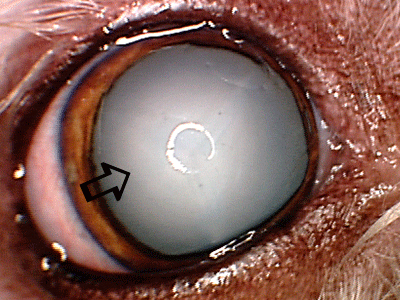

Mature diabetic cataract in a Bichon. Cataract is abnormal change of the lens material resulting in the white milky appearance (arrow). Sometimes diabetic cataracts have rapid progression over the course of several weeks or even days resulting in sudden onset of vision loss. Rapidly progressive cataracts can be very dangerous due to inflammation and irritation they can cause, and in some cases may result in the acute glaucoma development. If you detect sudden onset of vision loss or white eye milky appearance, contact your veterinarian immediately so eye can be evaluated.

Mature diabetic cataract in a Bichon. Cataract is abnormal change of the lens material resulting in the white milky appearance (arrow). Sometimes diabetic cataracts have rapid progression over the course of several weeks or even days resulting in sudden onset of vision loss. Rapidly progressive cataracts can be very dangerous due to inflammation and irritation they can cause, and in some cases may result in the acute glaucoma development. If you detect sudden onset of vision loss or white eye milky appearance, contact your veterinarian immediately so eye can be evaluated.